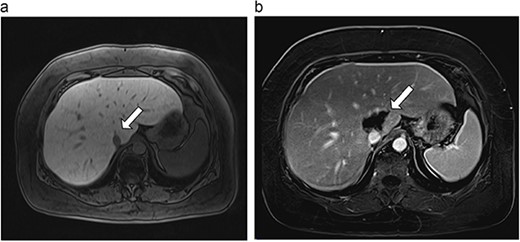

Six patients with six primary or secondary tumors of the caudate lobe were identified (Table 1). Median age at diagnosis was 68 years (51–77 years); two patients were female. Primary disease process was colon adenocarcinoma (n = 4; Figs 3–6), hepatocellular carcinoma (HCC; n = 1; Fig. 7) and metastatic pancreatic neuroendocrine tumor (n = 1; Fig. 8). All patients with colon adenocarcinoma received systemic therapy with 5-fluorouracil, oxaliplatin, and leucovorin (FOLFOX) prior to microwave ablation of hepatic metastases. The patient with metastatic neuroendocrine tumor had progression of hepatic metastases on lanreotide prior to microwave ablation. The patient with HCC had previously been treated with transarterial embolization and cryoablation of tumors, but had recurrence of disease, which was managed with microwave ablation.

| 4 (6a,b) | 51, M | Colon adenocarcinoma | 6 cycles FOLFOX | 4 | Laparoscopic microwave ablation | 14 | 23.8 | 9.8 | 13 | Yes |

(a) Pre-ablation MRI demonstrating 14 mm lesion in caudate lobe of liver. (b) Post-ablation MRI (23 days postoperatively) demonstrating 23.8 mm complete ablation of caudate lesion.

Postoperative MRIs were obtained at a median of 19 days postoperatively (14–23 days). Median ablation margin (difference between ablation zone and original tumor size) was 22.95 mm (9.3–34.4 mm). At a median follow-up of 10.5 months (6–15 months), one of six (17%) caudate ablations had evidence of local recurrence. At diagnosis, this tumor had been abutting 180 degrees of the vena cava, and its proximity to the posterior hilum made a more aggressive burn inadvisable. Time to recurrence for this patient was 6 months. There were no recurrences in non-caudate ablations in this same patient. No long-term complications were observed in any patients.